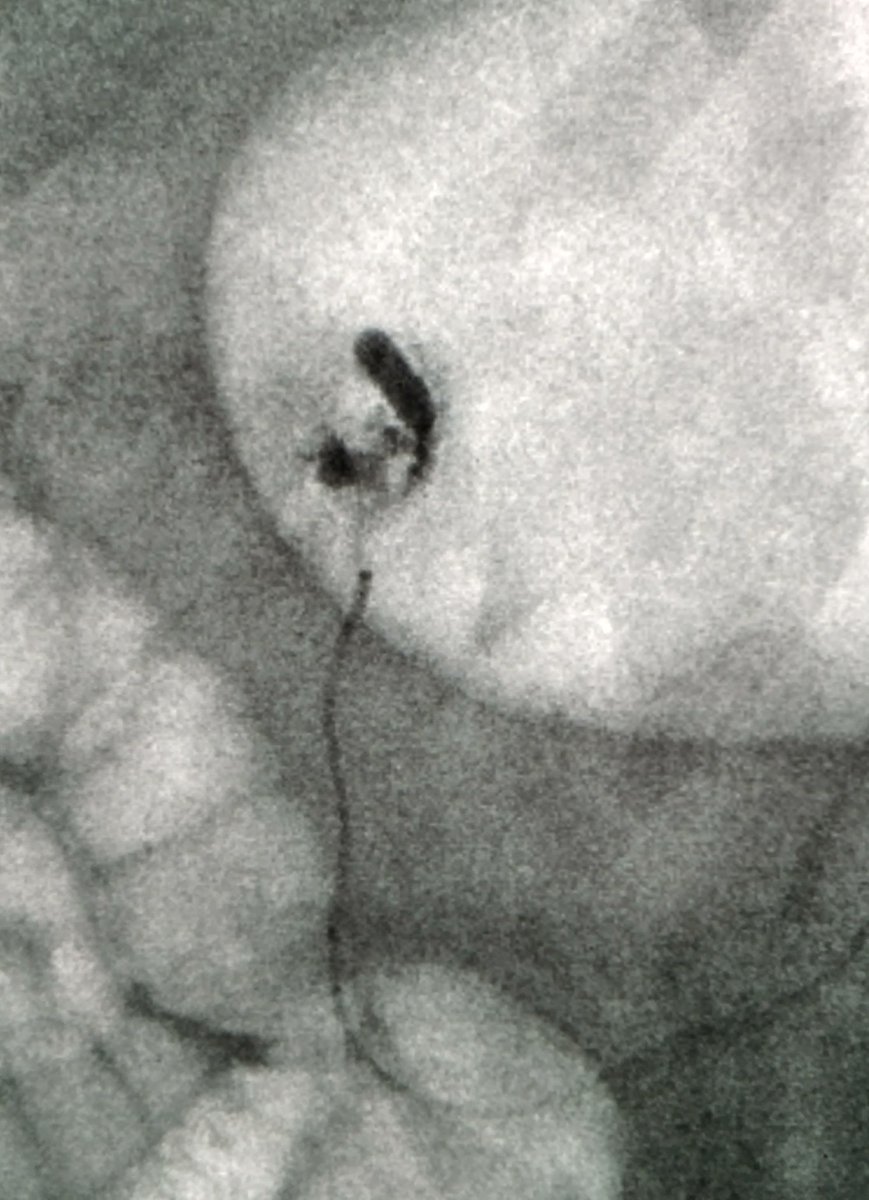

Unstable pt GDA bleed on scope Cool, I'll embo Aorta's occluded Cool, I'll go radial Radial is 1 mm Cool, I'll go ulnar Celiac is occluded Cool, I'll go transcollat via SMA Can't pass bleed to coil Cool, I'll glue Stable, ready 4 d/c this week #IRad is Cool ๐Ÿ˜Ž Society of Interventional Radiology

Unstable pt GDA bleed on scope

Cool, I'll embo

Aorta's occluded

Cool, I'll go radial

Radial is 1 mm

Cool, I'll go ulnar

Celiac is occluded

Cool, I'll go transcollat via SMA

Can't pass bleed to coil

Cool, I'll glue

Stable, ready 4 d/c this week